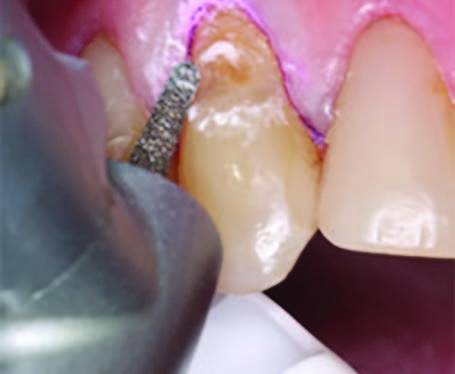

Figure 4. Preparation of the lesion is completed with diamond bur and starburst beveling pattern to enhance aesthetic blending.